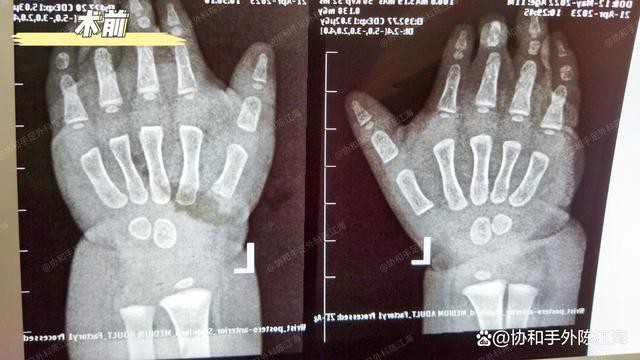

צילום רנטגן לפני ניתוח